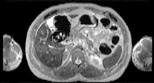

Visible Human male: Sectio transversalis 1563

CT

NMR

Pd                          / T2 \                         T1